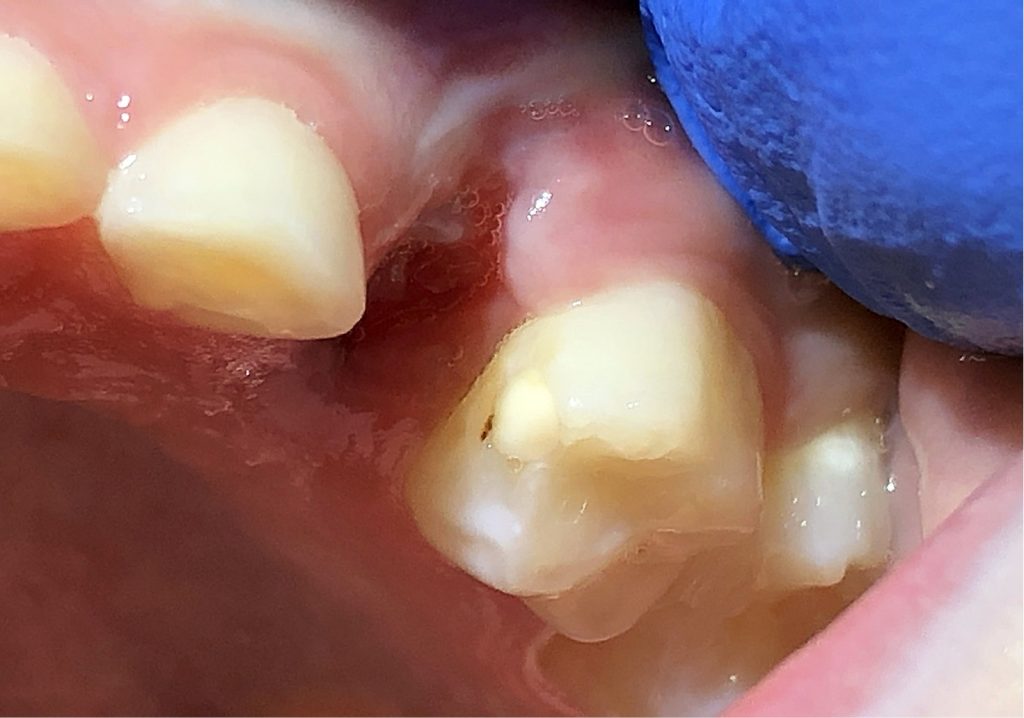

- Opis przypadku 7-letniego pacjenta.

W niniejszej pracy przedstawiono znaczenie podejścia interdyscyplinarnego i trudności w leczeniu 7-letniego pacjenta z deficytem dehydrogenazy acylo-koenzymu A średniołańcuchowych kwasów tłuszczowych.